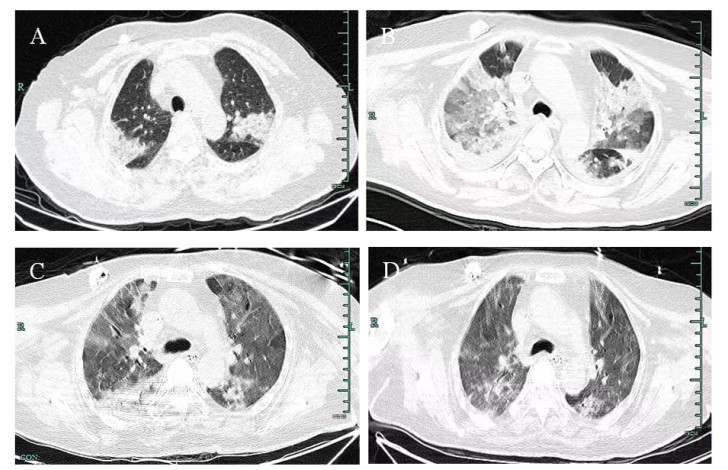

1 病例资料病例1为女性,40岁,因“发热伴咳嗽咳痰8 d,加重1 d”于2022-12-23入院。患者8 d前无明显诱因出现畏寒发热,体温未监测(最高体温不详),伴咳嗽咳痰,为白色粘痰,痰少不易咳出,无明显胸闷气闭,无胸痛咯血,无恶心呕吐,无腹痛腹泻及其他不适,期间未正规就诊,自行服用“安乃近”后体温可下降(具体不详)。1 d前患者自觉上述症状加重,伴有胸闷气闭等不适,由家属送至当地医院,完善动脉血气分析及胸部CT检查,诊断考虑为“急性呼吸衰竭、肺部感染”,予气管插管及对症支持治疗后,建议转上级医院进一步诊治,遂至本院就诊。急诊胸部CT:⑴两肺多发感染伴实变,双侧少量胸腔积液,纵隔多发稍大淋巴结。⑵心包少量积液。急诊拟“重症肺炎、急性呼吸衰竭”收住重症医学科。患者既往体健,否认吸烟、饮酒史,有新冠疫苗接种史。入科查体:体温38.5℃,呼吸24次/min,脉搏101次/min,血压123/61 mmHg(1 mmHg=0.133 kPa)。意识药物镇静,经口气管插管接呼吸机辅助通气(AC+PC模式,FiO2:100%,PEEP:10 cmH20),血氧饱和度93%。全身皮肤、巩膜无黄染,锁骨上下淋巴结未触及肿大,双下肺呼吸音低,闻及散在湿啰音,未闻及哮鸣音。心脏听诊无特殊,腹平软,肝脾肋下未触及,移动性浊音(-),肠鸣音3次/min,双下肢无水肿。进行实验室检查,动脉血气分析(呼吸机纯氧支持):pH 7.482,氧分压74.2 mmHg,二氧化碳分压38.6 mmHg,碳酸氢根28.6 mmol/L,剩余碱5.2 mmol/L,乳酸1.1 mmol/L。血常规:WBC 14.5×109/L,NEU% 95.1%,L% 2.6%;CRP 285.52 mg/L;PCT 1.75 ng/mL;肝功能:ALT 70 U/L,AST 225 U/L,ALB 22.5 g/L;CK 7114 U/L,LDH 904 U/L;肾功能正常;凝血功能:PT 14.6 s,INR 1.23 s,PT活动度67%,FIB 11.49 g/L,D-二聚体7.17 mg/L;甲流、乙流、禽流感病毒、腺病毒、呼吸道合胞病毒均为阴性,新型冠状病毒核酸检测阴性。进行辅助检查,急诊胸部CT提示:⑴两肺多发感染伴实变,双侧少量胸腔积液,纵隔多发稍大淋巴结;⑵心包少量积液(图 1A)。初步诊断:⑴重症肺炎;⑵急性呼吸衰竭;⑶肝功能不全;⑷双侧胸腔积液(少量);⑸低蛋白血症。治疗上予莫西沙星(0.4 g ivgtt qd)联合亚胺培南西司他丁(1.0 g ivgtt q8h)抗感染,同时予呼吸机支持、镇痛镇静、俯卧位通气、激素抗炎、低分子肝素抗凝、化痰解痉、保肝护胃、维持内环境稳定及对症支持治疗,定期行新型冠状病毒核酸检测。为进一步查明病因、明确诊断,经家属同意后于2022-12-24行支气管镜检查并采集支气管肺泡灌洗液(bronchoalveolar lavage fluid,BALF)送南京华大医学检验所行宏基因组二代测序(metagenomic next-generation sequencing,mNGS)。2022-12-26本院新型冠状病毒核酸检测阳性,2022-12-27 mNGS结果显示找到鹦鹉热支原体,序列数为72条,相对丰度7.24%。追问病史,患者为农民,家中常年饲养鸡、鸭等家禽,否认饲养及接触鹦鹉、鸽子等其他鸟类。结合患者病史、症状、胸部影像学及mNGS结果,考虑患者为新冠疫情开放期间在家感染鹦鹉热衣原体并导致重症肺炎,院内感染新型冠状病毒,因本院药房无多西环素,遂予阿奇霉素(0.5g ivgtt qd)联合莫西沙星(0.4g ivgtt qd)抗感染,停用亚胺培南西司他丁针,予对因治疗后患者血炎症指标及体温明显下降。2023-01-06复查胸部CT提示两肺多发感染伴实变,对比2022-12-23感染部分吸收,胸腔积液增多(图 1B),予胸腔穿刺闭式引流及调整抗感染治疗。2023-01-16再次行肺泡灌洗送检mNGS,结果提示鲍曼不动杆菌、肺炎克雷伯菌、洋葱伯克霍尔德菌、大肠埃希菌、鹦鹉热衣原体感染,序列数分别为69 120、19 228、775、200、7条,结合患者病情及鹦鹉热衣原体序列经治疗后较前明显减少,予停用阿奇霉素。2023-01-18复查胸部CT提示两肺多发感染伴实变,对比2022-12-23感染部分吸收,两肺上叶空洞形成(图 1C)。考虑患者短期内无拔管指征,于2023-01-12行暂时性气管切开,逐步开始呼吸肌功能锻炼。患者炎症指标逐步下降,自主呼吸趋于平稳,于2023-01-18顺利脱机,期间复查患者胸部影像学表现提示感染逐步吸收,病情平稳后于2023-01-28转到呼吸内科普通病房继续治疗。转入普通病房后,在家属的陪伴下,患者逐渐恢复饮食并拔除胃空肠营养管,最终于2023-02-14顺利出院。2023-05-09门诊复查胸部CT提示两肺见散在絮状、条索状及片状密度增高影,两肺上叶薄壁肺空洞(图 1D)。

| A:双下肺大面积实变;B:感染较前吸收,右侧胸腔积液增多;C:感染较前吸收,右上肺可见空洞形成;D:右上肺薄壁空洞 图 1 病例1胸部CT检查结果 |